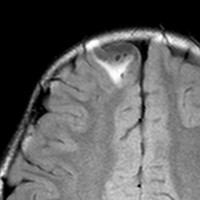

画像診断

- とても難しいといえます,特徴的な所見がないからです

- ほとんどが髄膜に接する脳表を巻き込む病変なのです

- 小さな多房性のう胞を伴ったり,脳内に結節とのう胞を形成するものもあります

- T1強調では等信号から低信号

- T2強調画像では低信号領域と血管のflow-voidがみられます

- ガドリニウム増強では不規則な増強像を見ることが多いです

- T2低信号の部分(結節)が強くガドリニウム増強されることも特徴かもしれません

難治性てんかんで発症した小児ですが,どう見てもDNTなのかなと思います。石灰化もありません。一般的に,meningioangiomatosisの術前診断は困難であると言えます。いずれにしても治療はlesionectomyです。